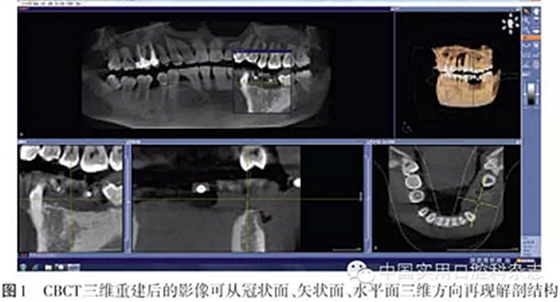

CT是20世紀(jì)70年代初放射診斷的一項(xiàng)重大突破。CT的多平面重組(multi-planar reformatting,MPR)和三維(3D)重組技術(shù)可將軸向、冠向和矢狀面斷層數(shù)據(jù)重組,進(jìn)行多層橫截面斷層重建全景圖像,因而成為目前口腔種植最理想的放射線檢查技術(shù)[1]。最初的CT技術(shù)所需的放射線劑量很大,金屬會(huì)產(chǎn)生散射偽影,通常需要第三方軟件才能實(shí)現(xiàn)數(shù)據(jù)的導(dǎo)出和導(dǎo)入,儀器價(jià)格昂貴,必須要有經(jīng)過特殊培訓(xùn)的專業(yè)人員才能操作。錐形束CT(cone beam computed tomography,CBCT)是20世紀(jì)90年代末發(fā)展起來的一種三維成像技術(shù),1998年首次報(bào)道了口腔頜面CBCT[2]。CBCT用三維錐形束X線掃描代替扇形束的螺旋CT掃描,獲得的直接數(shù)據(jù)是二維數(shù)據(jù),重建后得到三維圖像,因此金屬偽影小、重組數(shù)據(jù)的精確度高。CBCT的出現(xiàn)徹底改變了傳統(tǒng)口腔頜面放射學(xué)設(shè)備僅能提供二維圖像的歷史,可以三維顯示病變結(jié)構(gòu),大大提高了診斷能力(圖1)。CBCT已廣泛應(yīng)用于口腔種植術(shù)前診斷與設(shè)計(jì)、牙體牙髓病、牙周疾病、顳下頜關(guān)節(jié)疾病、口腔頜面部骨折和腫瘤等領(lǐng)域,在三維測(cè)量、診斷分析方面已經(jīng)取代了傳統(tǒng)的放射線檢查技術(shù)。